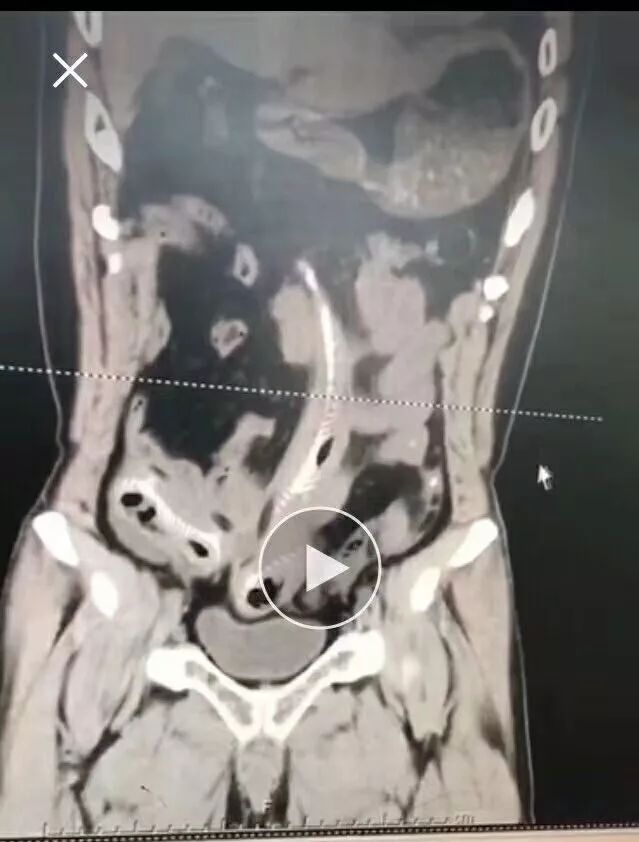

CT三维重建下三条泥鳅的骨骼清晰可见

占据整个下腹部和盆腔......

2月10日那天我看的急诊,事情的经过是这样的,我是他的首诊大夫,一开始急诊打电话急会诊说是吃泥鳅吃坏了肚子,我觉得这也没啥,然后让他做腹部CT。后来看到他的CT赫然三条鱼骨头。我一看CT很吃惊,难道是生吃的?

去一楼急诊问患者本人,当时我听他说了事实,是下面塞进去的真把我吓一跳。他第一句话就是说,听信网上前列腺偏方把他害惨了,让我救救他赶紧手术,问我有没有穿孔,当时只有一个小时,还早,摸着板状腹很硬。他意识还有,后来就慢慢感染中毒休克了。后来术中发现乙状结肠穿孔,三条鱼都到了腹腔里,有一条还往回盲部钻,不过取出来应该都是死的了。